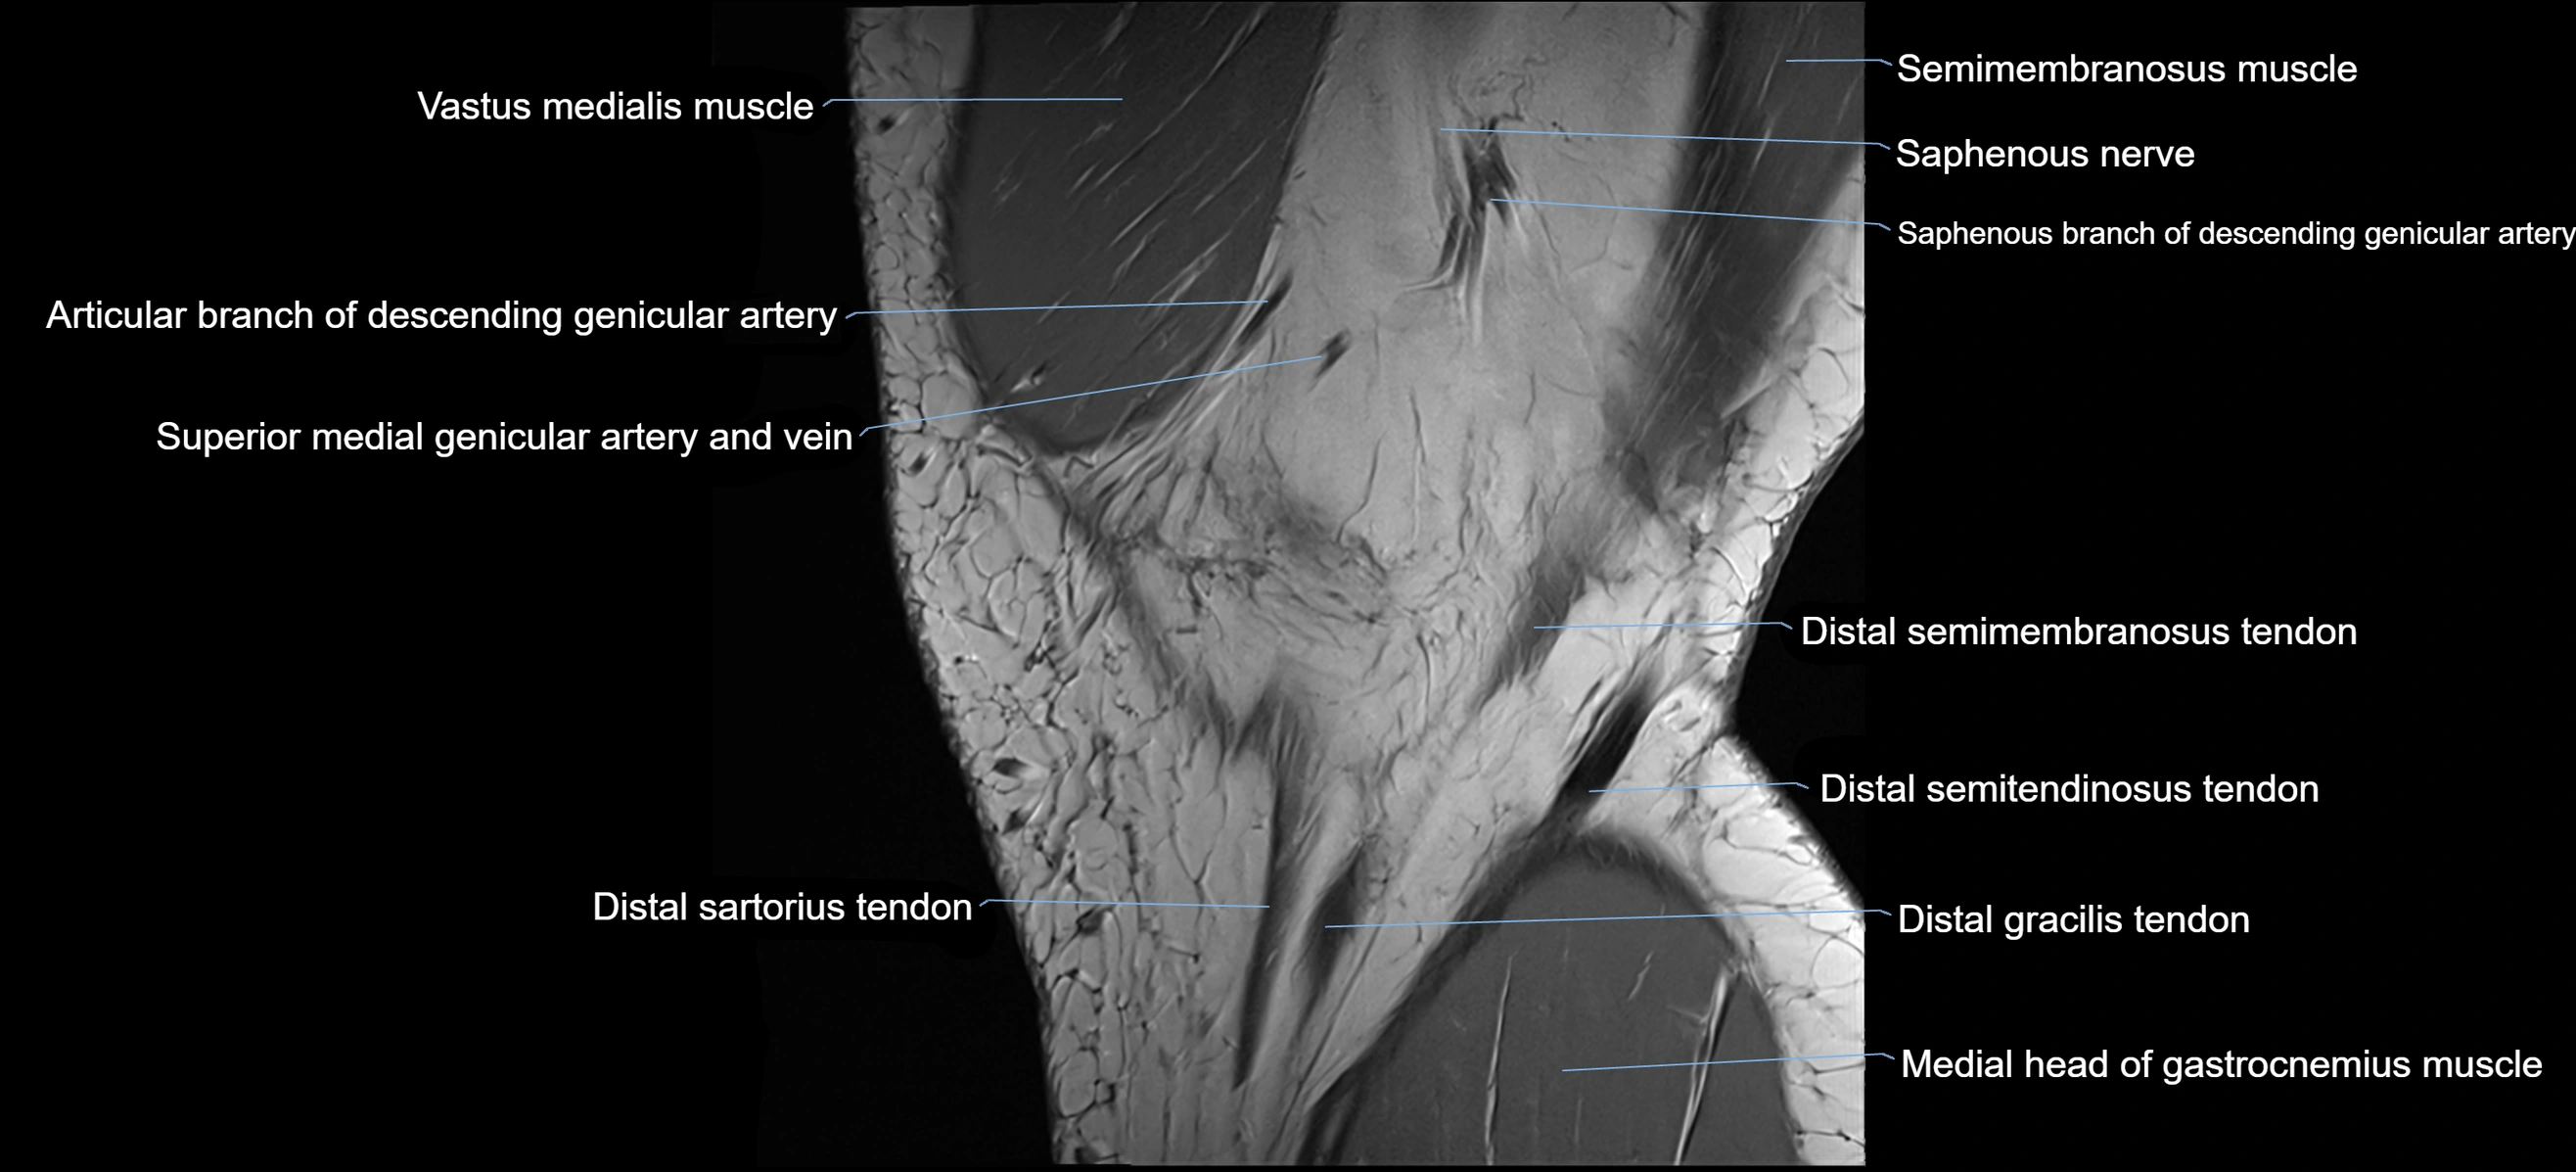

- Distal semimembranosus tendon

- Distal semitendinosus tendon

- Gracilis tendon (Distal)

- Medial gastrocnemius tendon

- Medial head of gastrocnemius muscle

- Saphenous nerve

- Sartorius tendon (Distal)

- Semimembranosus muscle

- Superior medial genicular artery

- Superior medial genicular vein